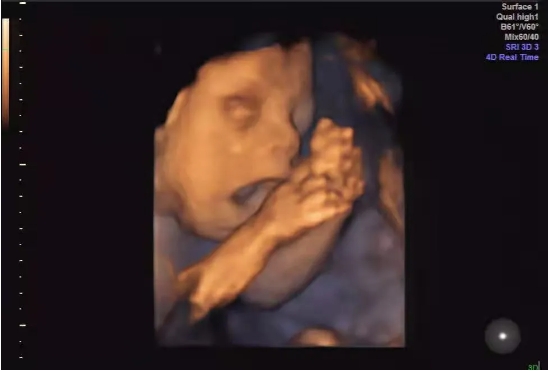

四维彩超能够对胎儿发育情况进行全方位 “扫描”。它不仅能够像一位技艺精湛的雕塑家,立体地呈现胎儿面部、四肢发育状况,还能像一位细心的观察者,清晰显示泌尿系统、消化系统、胸腔及脑部结构。更为神奇的是,它能对胎儿实时活动通过动态图像反映出来,在胎儿畸形鉴别方面价值极高。比如,通过观察胎儿的面部表情和肢体动作,医生可以初步判断胎儿的神经系统发育是否正常;通过观察胎儿的吞咽动作,了解消化系统的功能情况。